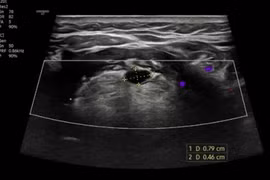

Rò khe mang là dị tật bẩm sinh vùng cổ bên được chỉ định điều trị phẫu thuật để lấy bỏ toàn bộ đường rò. Việc phẫu thuật cần thực hiện tại cơ sở y tế có đầy đủ trang thiết bị để hạn chế biến chứng nguy hiểm.